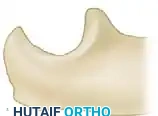

Bony Debridement and Impingement Clearance

Soft-tissue release alone is often insufficient if osseous impingement exists. The surgeon must dynamically test the elbow and address any bony blocks.

- Completely extend the elbow. If extension remains incomplete despite a full anterior capsulectomy, the limitation is likely osseous.

- Debride the olecranon fossa, removing any fibrotic scar tissue or loose bodies.

- Resect the tip of the olecranon using a sharp osteotome or rongeur, and clear any osteophytic enlargement along the margins of the olecranon fossa that may be impinging during terminal extension.

- Next, flex the elbow. If flexion to 135 degrees is impossible, investigate the anterior compartment for osseous impingement.

- Remove any dense scar tissue, loose bodies, or osteophytes located in or around the coronoid fossa and the radial fossa. Excision of the tip of the coronoid process may occasionally be necessary to maximize terminal flexion.